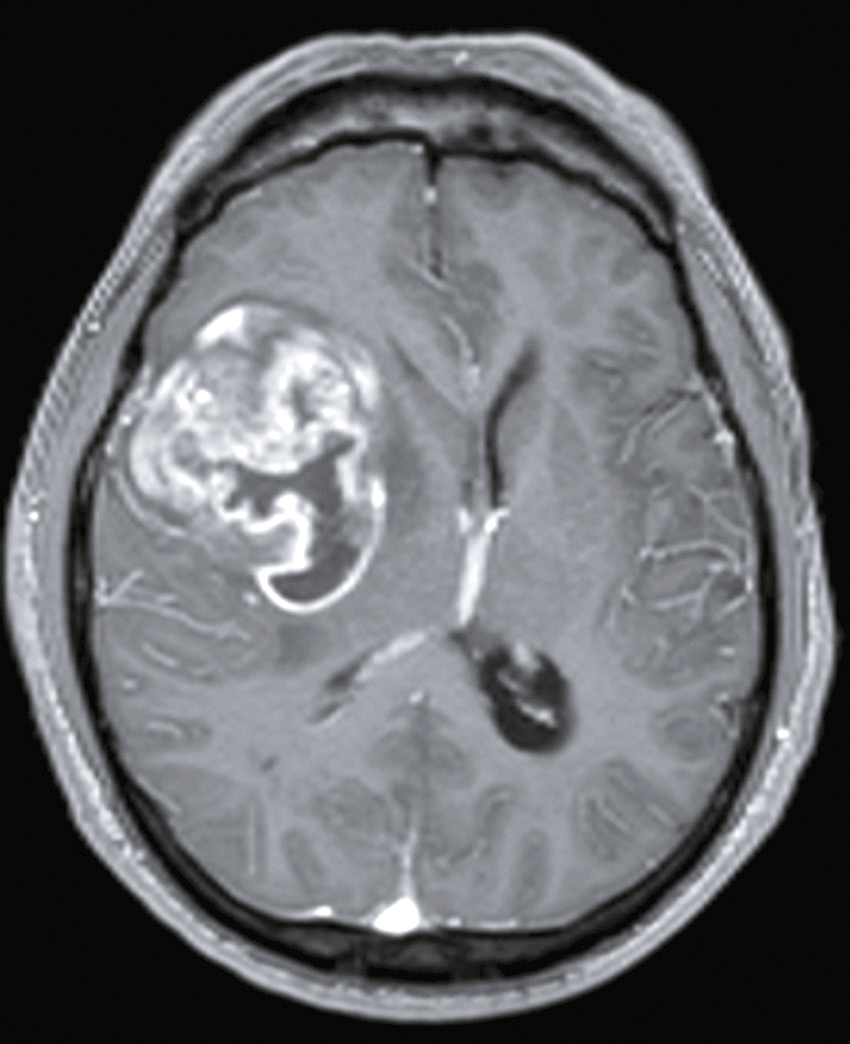

Vous débutez un traitement par benzodiazépine, vitaminothérapie B1, B6, PP, réhydratation par sérum salé et immunoglobulines polyvalentes intraveineuses associées à une héparine de bas poids moléculaire à dose isocoagulante. Le lendemain matin, le patient s’est aggravé d’un point de vue clinique. Il n’a plus d’hallucination visuelle mais il présente maintenant une tétraparésie évaluée à 3/5 avec ataxie des quatre membres, une dysarthrie, des troubles de la déglutition, et une ophtalmoplégie bilatérale. Un bilan biologique a été prélevé avant votre arrivée : numération formule sanguine : Hb : 13,8 g/dL, leucocytes : 8 600/ mm3, plaquettes : 332 000/mm3, ionogramme sanguin : Na+ : 142 mmol/L, K+ : 4,2 mmol/L, clairance de la créatininémie : 92 mL/min, glycémie : 5,8 mmol/L, transaminases, phosphatases alcalines, bilirubines et γ-GT normales, CRP : 3 mg/L.

Une IRM cérébrale a été également réalisée (fig. 31.4). Quelle est la séquence présentée ?

L'image montre une IRM (Imagerie par Résonance Magnétique) du cerveau humain en coupe axiale, c'est-à-dire une vue transversale du cerveau prise horizontalement. Cette image est particulièrement intéressante car elle permet de visualiser les structures internes du cerveau avec une grande précision. On peut observer les globes oculaires en haut de l'image, qui apparaissent comme deux cercles blancs. Les différentes zones du cerveau sont visibles, avec des variations de teintes qui indiquent les différentes densités des tissus cérébraux. La région centrale lumineuse correspond au tronc cérébral, une structure cruciale pour de nombreuses fonctions vitales. Les zones plus sombres autour du tronc cérébral représentent les hémisphères cérébraux. Cette image est utilisée pour diagnostiquer et évaluer diverses conditions neurologiques, telles que les tumeurs, les accidents vasculaires cérébraux, les infections, et les anomalies structurelles. L'IRM est une technique non invasive qui utilise des champs magnétiques et des ondes radio pour produire des images détaillées des organes et des tissus internes.

- A T1

- B écho de gradient

- C T2

- D T2/FLAIR

- E diffusion